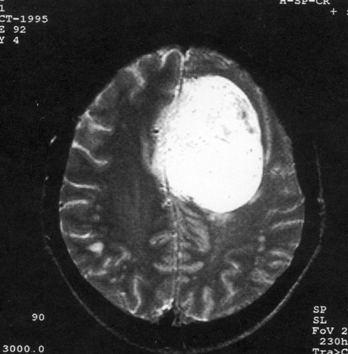

问题 病历摘要:??患者,男,40岁。发作性左下肢抽搐1年余,每次发作3~5分,每周发作1~2次。每次发作后感左下肢乏力,约半日后可自行恢复。既往身体健康。体检:神清,头顶部偏右有局限性骨性隆起(1.5×1.5cm),左鼻唇沟稍浅,伸舌居中。感觉、运动无明显异常。左浅反射减退,左下肢腱反射稍亢进,左Babinski征(-)。 脑膜瘤主要有哪些好发部位?